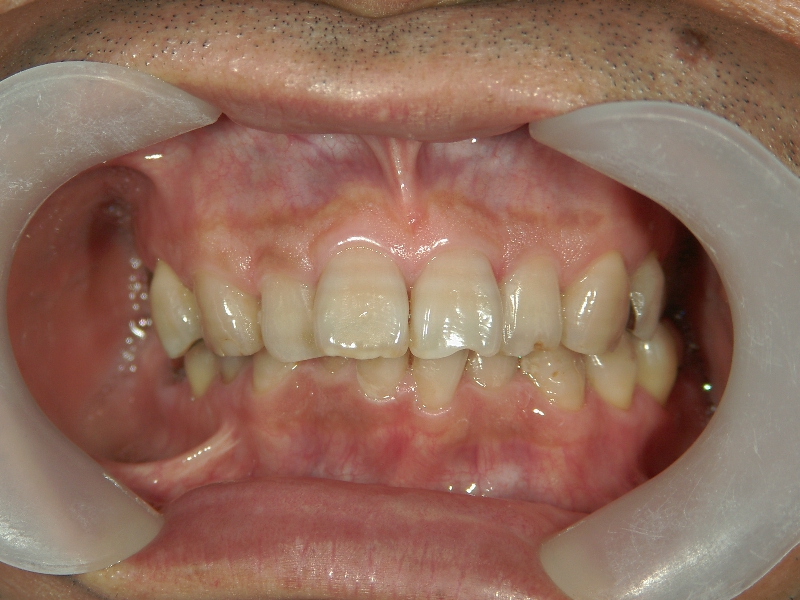

矯正歯科 治療前矯正歯科 治療前

46歳男性 浜松市浜北区在住

治療期間2年2ヶ月

主訴:下の歯がガタガタ。

矯正歯科 治療前 右上4番、左右下4番 計3本抜歯し、叢生を改善